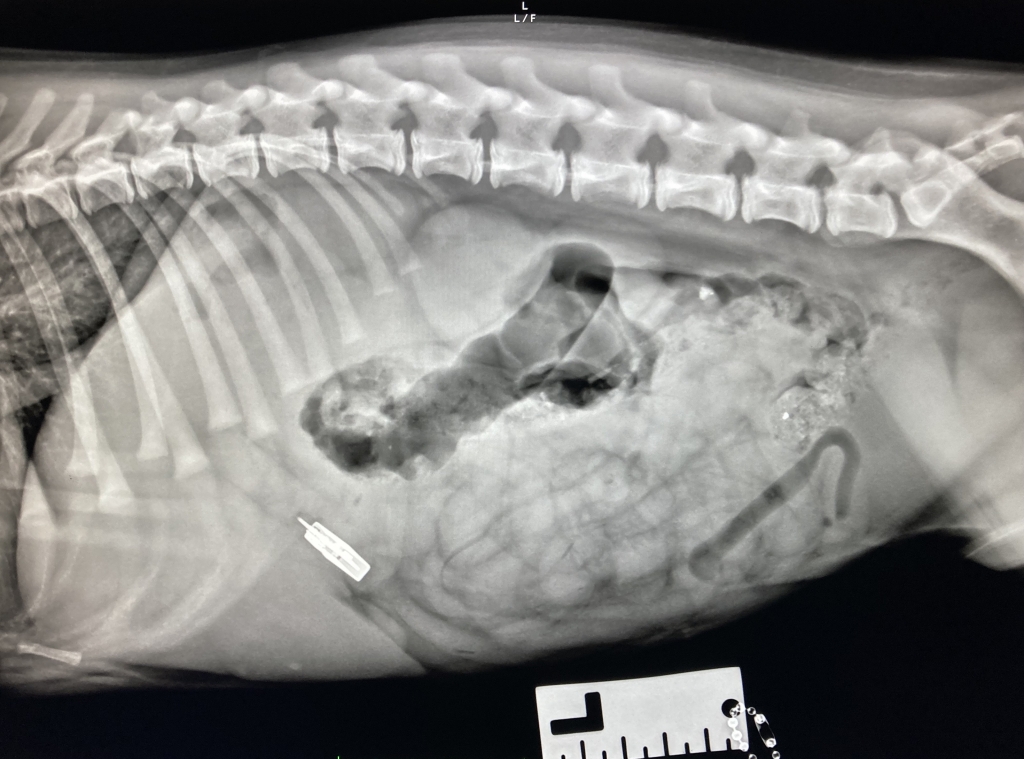

Paula explained: “We were told Billy had swallowed the Bluetooth USB and this was confirmed when we carried out an X-ray examination and an endoscopy examination, in which a thin tube containing a mini camera and micro tools is fed down the oesophagus.

“The problem was that the stick was making him sick but he couldn’t bring it back up, so we decided to use the endoscope to try to retrieve it. If we were unable to retrieve it, he would have needed life-saving surgery to remove the USB stick directly from his stomach.